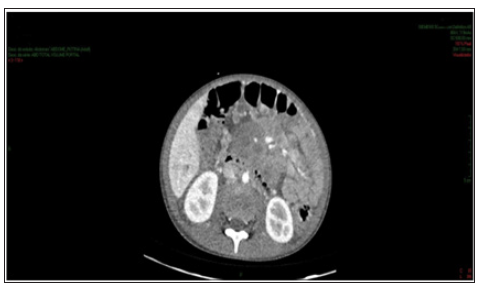

Figure 2: Contrast-enhanced abdomen CT showing expansive formation in the retroperitoneum and root of the mesentery compatible with lymph node conglomerate. Numerous and prominent para-aortic lymph nodes.

Enhanced abdominal CT performed on the 1st day of hospitalization, revealed enlarged liver, with heterogeneous attenuation, at the expense of diffuse, ill-defined, sparse hypodense images, measuring up to 2.4 cm in segment II. Mild dilation of the intrahepatic bile ducts. Spleen enlarged, heterogeneous texture, at the expense of diffuse hypodense images. A hypodense, amorphous, poorly delimited (Figure 1). Expansive formation located in retroperitoneum and mesenteric root with involvement of the mesenteric vessels, without determining stenosis of the same, consistent with lymph node conglomerate. Prominent para-aortic lymph nodes, measuring up to 2.6 x 1.4 cm (Figure 2). Moderate amount of free fluid in the abdominal cavity. Hypodense and hypocaptant mass of ill-defined limits on the right flank, compatible with lymph node mass (Figure 3). In chest CT no lymph node enlargement was been in the mediastinum. On the 3rd day of hospitalization, abdominal ultrasonography was also performed to corroborate the CT findings, evidencing an enlarged liver, diffusely heterogeneous with small hypoechoic solid nodules distributed in the hepatic parenchyma. Heterogeneous pancreas, with presence of solid hypoechoic nodule, adjacent to the body, measuring 2.3 cm, suggesting lifonodomegaly. Enlarged spleen with presence of multiple hypoechoic solid nodules of small dimensions. Moderate ascites. Solid mass on the right flank measuring approximately 10 cm suggestive of confluent lymph nodes. The left inguinal lymph node biopsy was analyzed by the simple “imprint” and “cell block”, the macroscopy of which describes a brownish, lobed and unctuous fragment measuring 1.3 x 0.6 x 0.4 cm. Microscopy showed a chronic/acute granulomatous inflammatory process containing multinucleated giant cells in the lymph node tissue. Special coloring by the PAS and Grocott method evidenced fungal structures suspected of Paracoccidioides (Figures 4 & 5).